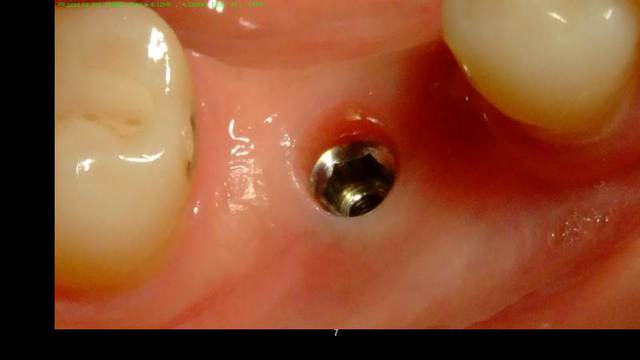

Cookie Consent byPrivacyPolicies.comInsertion immediate au niveau de 46 dans le septum - Eugenol

Insertion immediate au niveau de 46 dans le septum

Ici l'EII (extraction implantation immédiate) n'était pas indiquée à mon avis. Risque d'échec augmenté (suture ouverte) pour aucun bénéfice pour le patient.

Extraction, pose à 45 jours, implant plus large bien centré (meilleur profil d'émergence = hygiène facilitée).